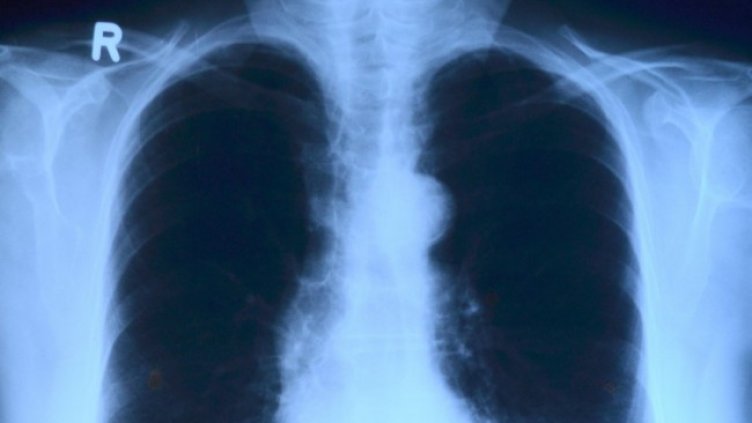

За да се постави диагноза костни метастази, най-често се извършва обстоен физикален преглед, последван от кръвни изследвания и образна диагностика (рентген/костна сцинтиграфия/компютърна томография/ЯМР/РЕТ скенер). В допълнение лекарят може да реши да направи и биопсия.